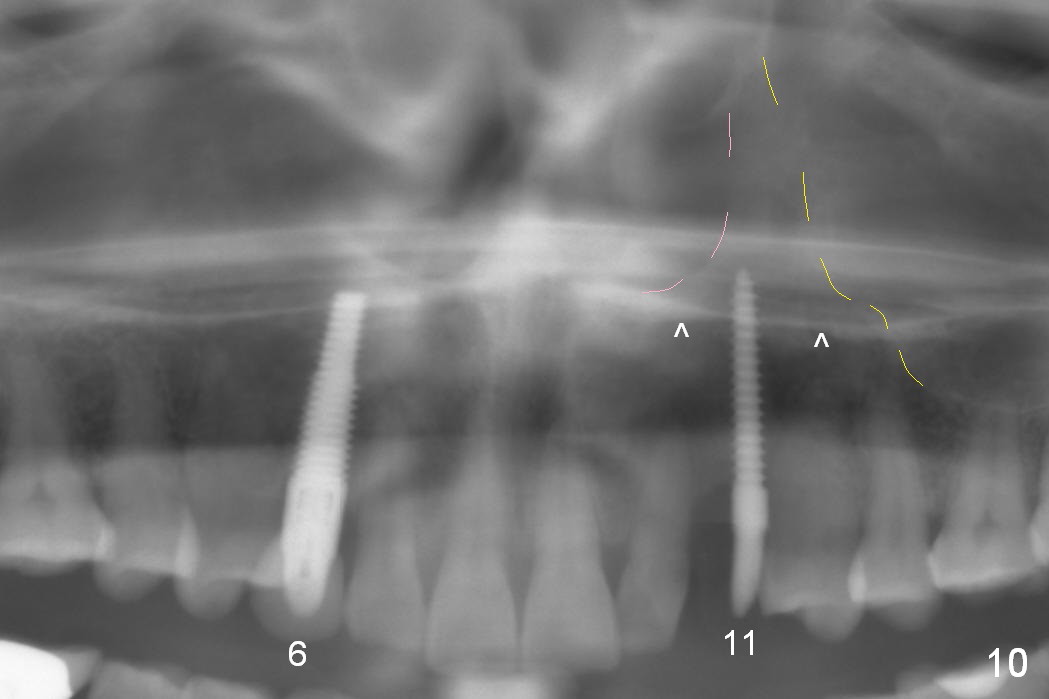

Eight months postop, the patient returns for #11 restoration. She reports no problem at #11, while there is light tenderness with a 2-piece implant (4.5x20 mm) at #6 at night (Fig.10, a portion of panoramic X-ray). Clinical exam reveals no abnormality at #6. Although the implant at #11 is buccally placed, there is no buccal plate atrophy (Fig.6,7). In fact the 20 mm 1-piece implant is placed in the bone (septum) between the nasal cavity (Fig.10 pink dashed line; Fig.13 (CBCT (52 year-old lady) N) and the maxillary sinus (yellow dashed line, S). In fact the apparent nasal floor indicated as arrowheads in Fig.2 and 10 is the horizontal plate of the palatine bone (hard palate)! Therefore there is no nasal floor perforation in this case. A long implant is indicated in the upper canine.